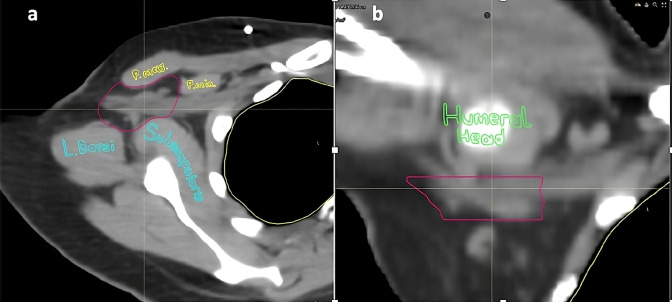

Materials and methods: Patients diagnosed with breast cancer and who were treated at Koç University Hospital between 2016 and 2022 and received RNI were included. BCRL was defined as a difference in arm circumference between the ipsilateral and contralateral limb >2.5 cm at any single encounter or ≥2 cm on ≥2 visits. ALTJ was retrospectively contoured, and doses were recorded as equivalent dose (α/β = 3).